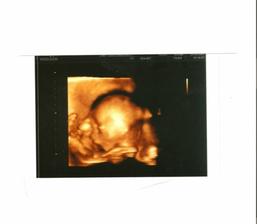

Samuelka jsem viděla, moc vyrostl a už vypadá jako macaté miminko (má 1500 gramů), i když ještě pořád má dost času...Je krásný, při utz na mě koukal a otvíral pusinku 🙂 Jen má stále dupku dole. Snad se stihne otočit. Kontrola 19.11.